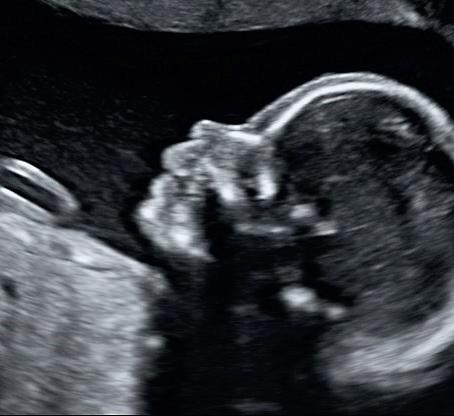

En 2D-scanning er den type scanning, du bliver tilbudt i det offentlige system. Her ser du et sort-hvidt profilbillede af barnet, som kan være lidt svært at aflæse, hvis man ikke har erfaring i det. Ved en 2D-scanning dannes der snitbilleder af barnets hjerne, hjerte, nyrer og andre organer.

Derfor anvendes 2D-scanning bl.a. til tidlige scanninger, misdannelses- og kønsscanninger, hvor man f.eks. gerne vil lave mål, se kønnet og bedømme barnets sundheds tilstand inde i maven.